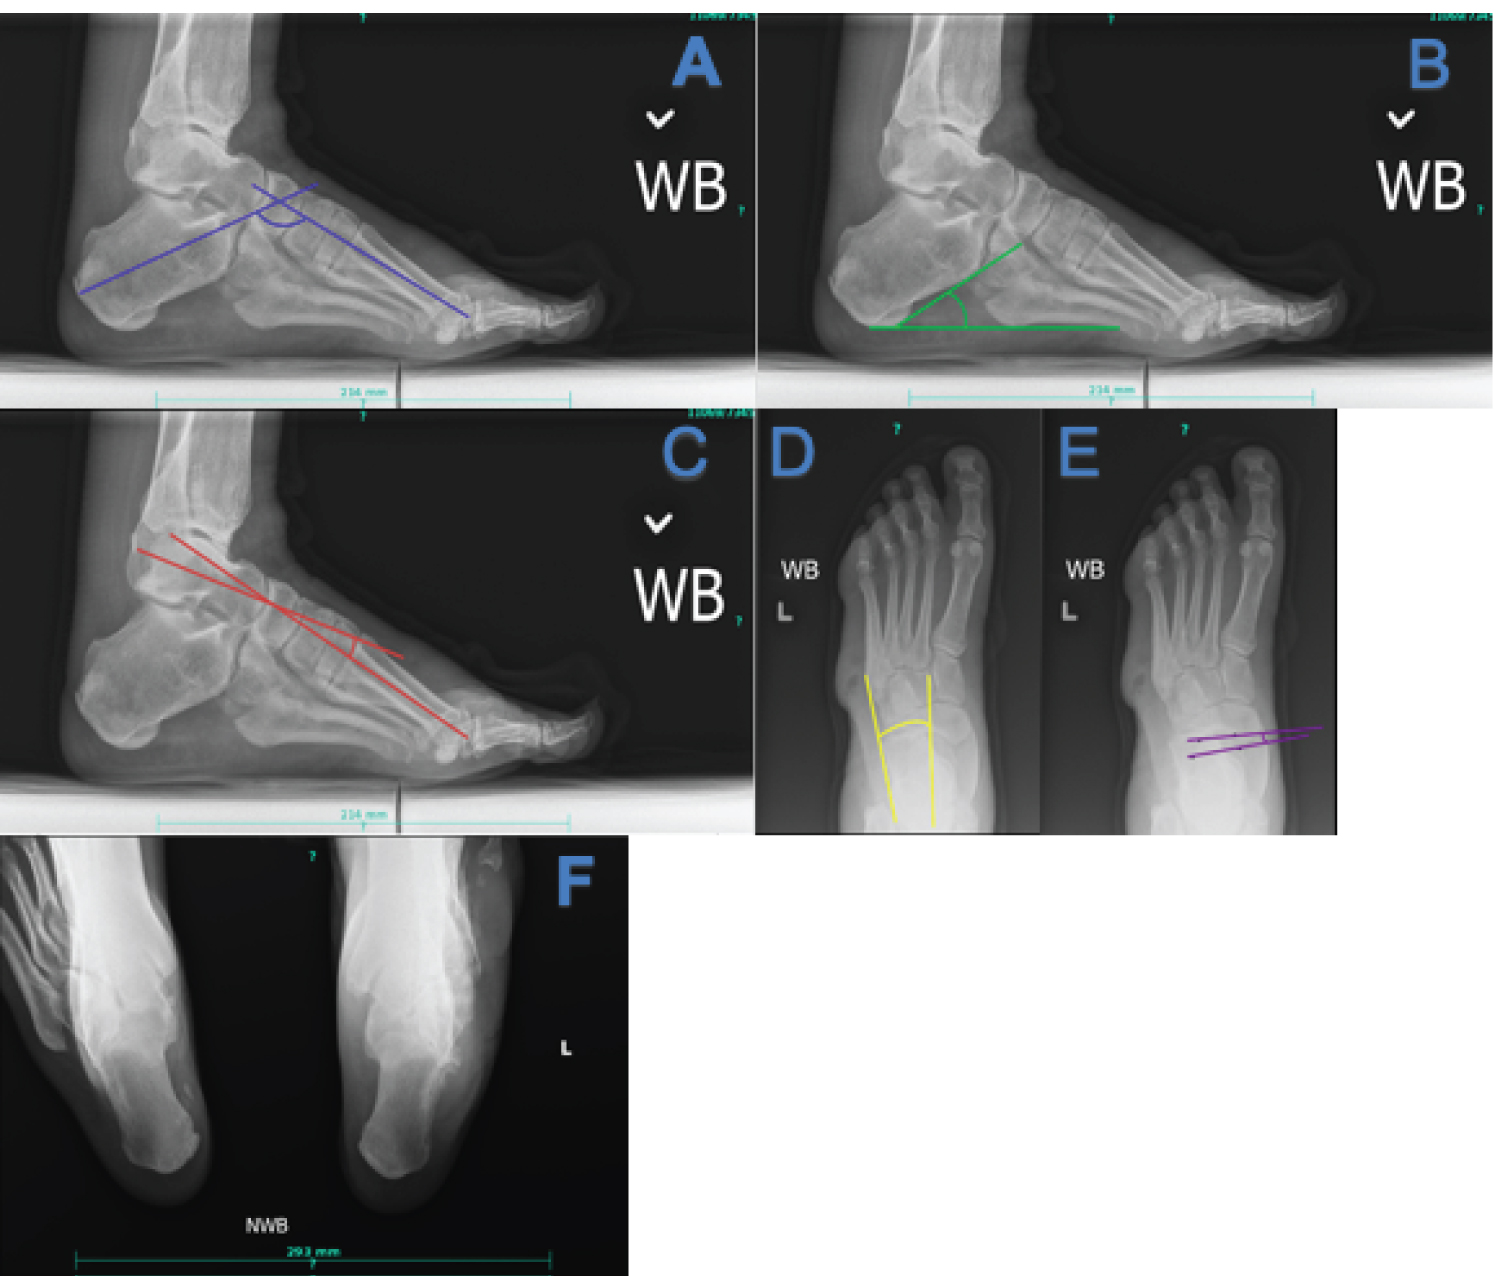

Plain film radiographs can be a powerful tool in assessing severity of deformity and preoperative planning. Hibbs angle, or the bisection of the long axis of the first metatarsal and calcaneus on a lateral projection, increases with increasing deformity, and an angle greater than 45 degrees is suggestive of pes cavus. Lateral Meary's angle, which consists of a bisection of the talus and 1st metatarsal, increases proportionally to the severity of cavus deformity. Normally the midline of the first metatarsal and talus are in line with each other, in cavus feet with an angle of greater than 4 degrees, with the convexity superior, correlates with pes cavus. Lateral calcaneal inclination increases with cavus deformity, with normal being 18 to 20 degrees. On an anterior-posterior (AP) view the talocalcaneal angle decreases with hindfoot varus seen in CMT. The talonavicular coverage angle increases with the cavus attitude of the foot. A long leg calcaneal axial has the benefit of allowing the leg-rearfoot-forefoot relationship to be assessed [30,31].

Figure 1: Key radiographic views and angles in CMT (a) Hibbs angle, decreased in cavus foot; (b) Calcaneal inclination angle, increased in cavus foot; (c) Lateral Meary's angle, increased in cavus foot; (d) AP talocalcaneal angle, decreased with hindfoot varus; (e) Talonavicular coverage angle, increased in cavus foot; (f) Long leg calcaneal axial view can be useful in determining the relationship of the calcaneus to the tibia. View Figure 1